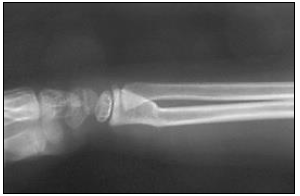

“Criança comparece ao atendimento após queda e apresenta a seguinte imagem radiográfica.”

A imagem anterior trata-se de uma fratura